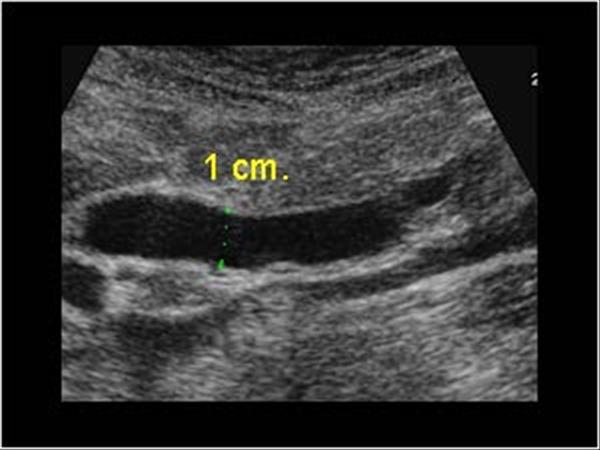

What is the measurement of the MPV?

less than 13 mm

What is possible if the MPV is more than 13 mm?

portal hypertension